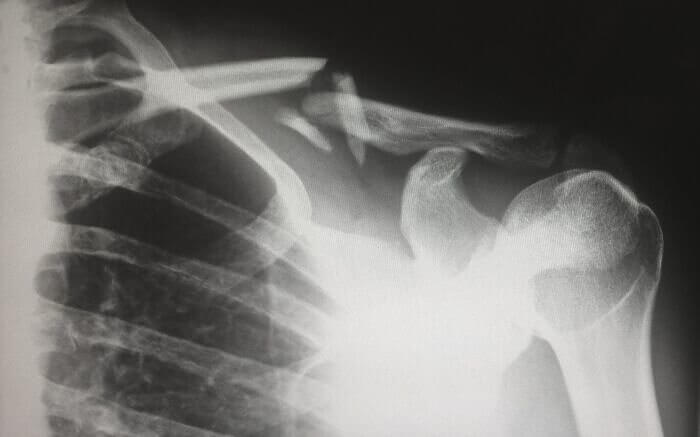

The Dark History of Pediatric X-Rays

It may feel like X-Rays have been around forever, but they really haven't. X-rays by pediatricians became commonplace in the early 1900s. Pediatricians began x-raying kids and the first thing they noticed was that many children had broken bones that had not been treated or set correctly. This led them to believe in a bone disease which they had been unaware of prior to using x-ray technology, but this was not the issue.

Sadly, the reason so many kids had broken bones was that many of the children were victims of physical abuse in their homes and nobody realized how widespread it was.